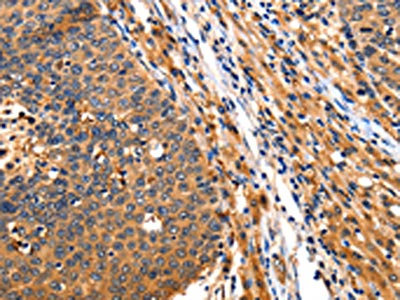

The image on the left is immunohistochemistry of paraffin-embedded Human gastic cancer tissue using CSB-PA073350(ITGAM Antibody) at dilution 1/10, on the right is treated with synthetic peptide. (Original magnification: ×200)

The image on the left is immunohistochemistry of paraffin-embedded Human liver cancer tissue using CSB-PA073350(ITGAM Antibody) at dilution 1/10, on the right is treated with synthetic peptide. (Original magnification: ×200)